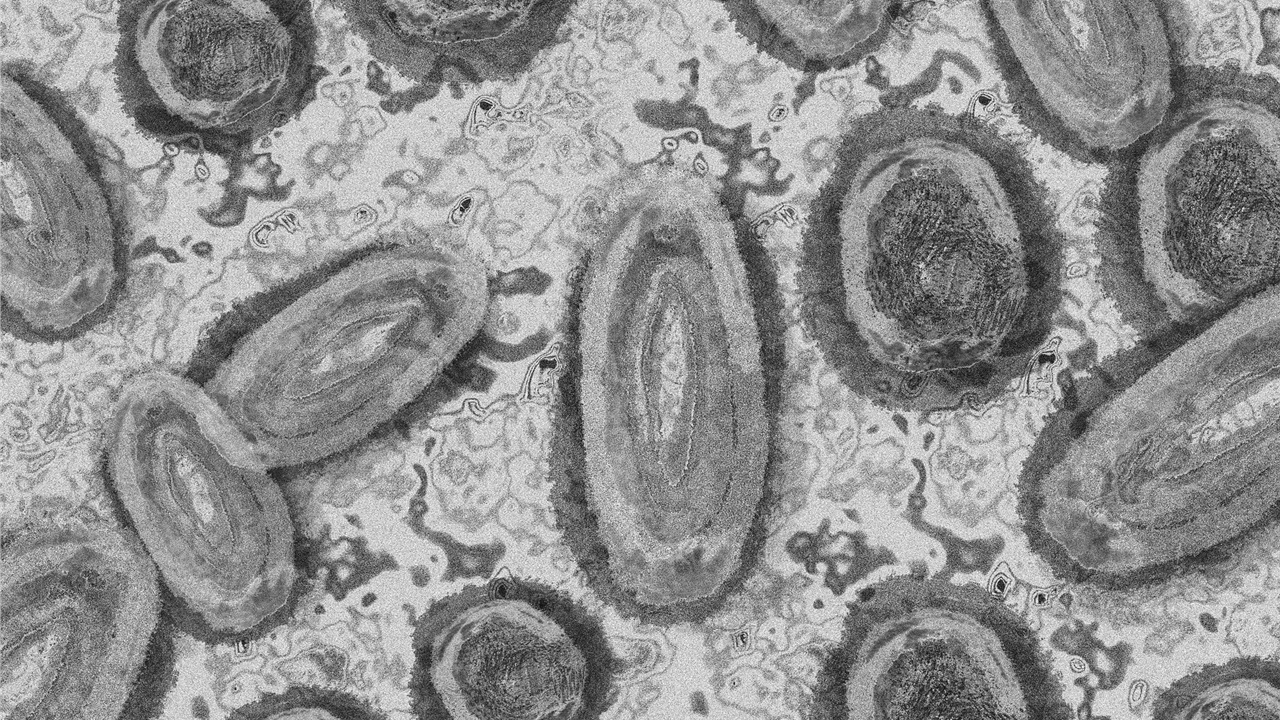

Φαίνεται πως υπάρχει κρούσμα ευλογιάς των πιθήκων και στη χώρα μας, αλλά ο κίνδυνος...

Έως τις 7 Ιουνίου είχαν καταγραφεί, παγκοσμίως, 1.088 επιβεβαιωμένα κρούσματα της...